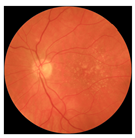

| No. | Fundus Image | Grad-CAM | Group | PRS | CNN | CNN+ML |

|---|---|---|---|---|---|---|

| 1 |  |  | Control | −1.07 | −0.57 | −1.95 |

| 2 |  |  | Control | −0.30 | −0.85 | −1.50 |

| 3 |  |  | Control | −3.12 | −1.53 | −1.83 |

| 4 |  |  | AMD | −0.99 | 0.29 | −0.86 |

| 5 |  |  | AMD | −0.23 | −0.29 | −0.66 |

| 6 |  |  | AMD | 0.17 | 1.31 | −0.75 |

| 7 |  |  | AMD | −0.43 | 1.16 | −0.48 |